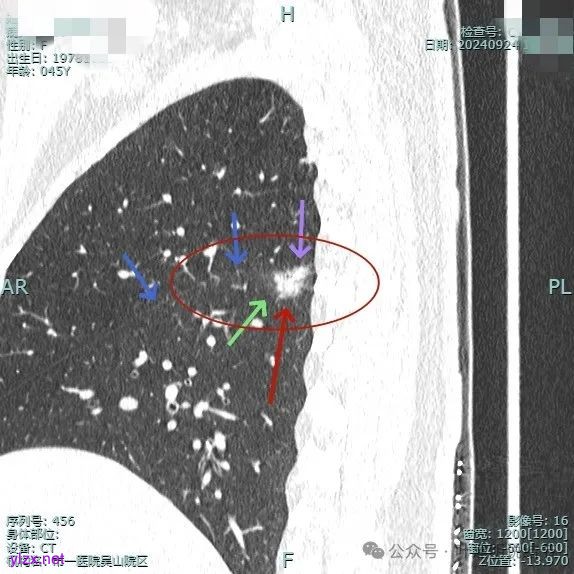

我们先来看2024年9月时的影像:

病灶1:

右下背段混合密度病灶,边上不太清爽,有片状淡磨玻璃影,实性部分密度较高。

感觉病灶有点晕征似的,表面不平,灶内不太致密。

有小血管进入,似有晕征。

离胸膜近但牵拉不明显,病灶边缘有细毛刺,较短且不太锐利。

边缘少许磨玻璃成分,血管进入明显。

瘤肺边界稍显不清。